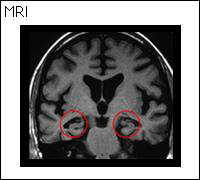

正常 アルツハイマー型認知症

アルツハイマー型認知症:全体的に脳が痩せて特に短期的記憶をつかさどる海馬が小さくなっている